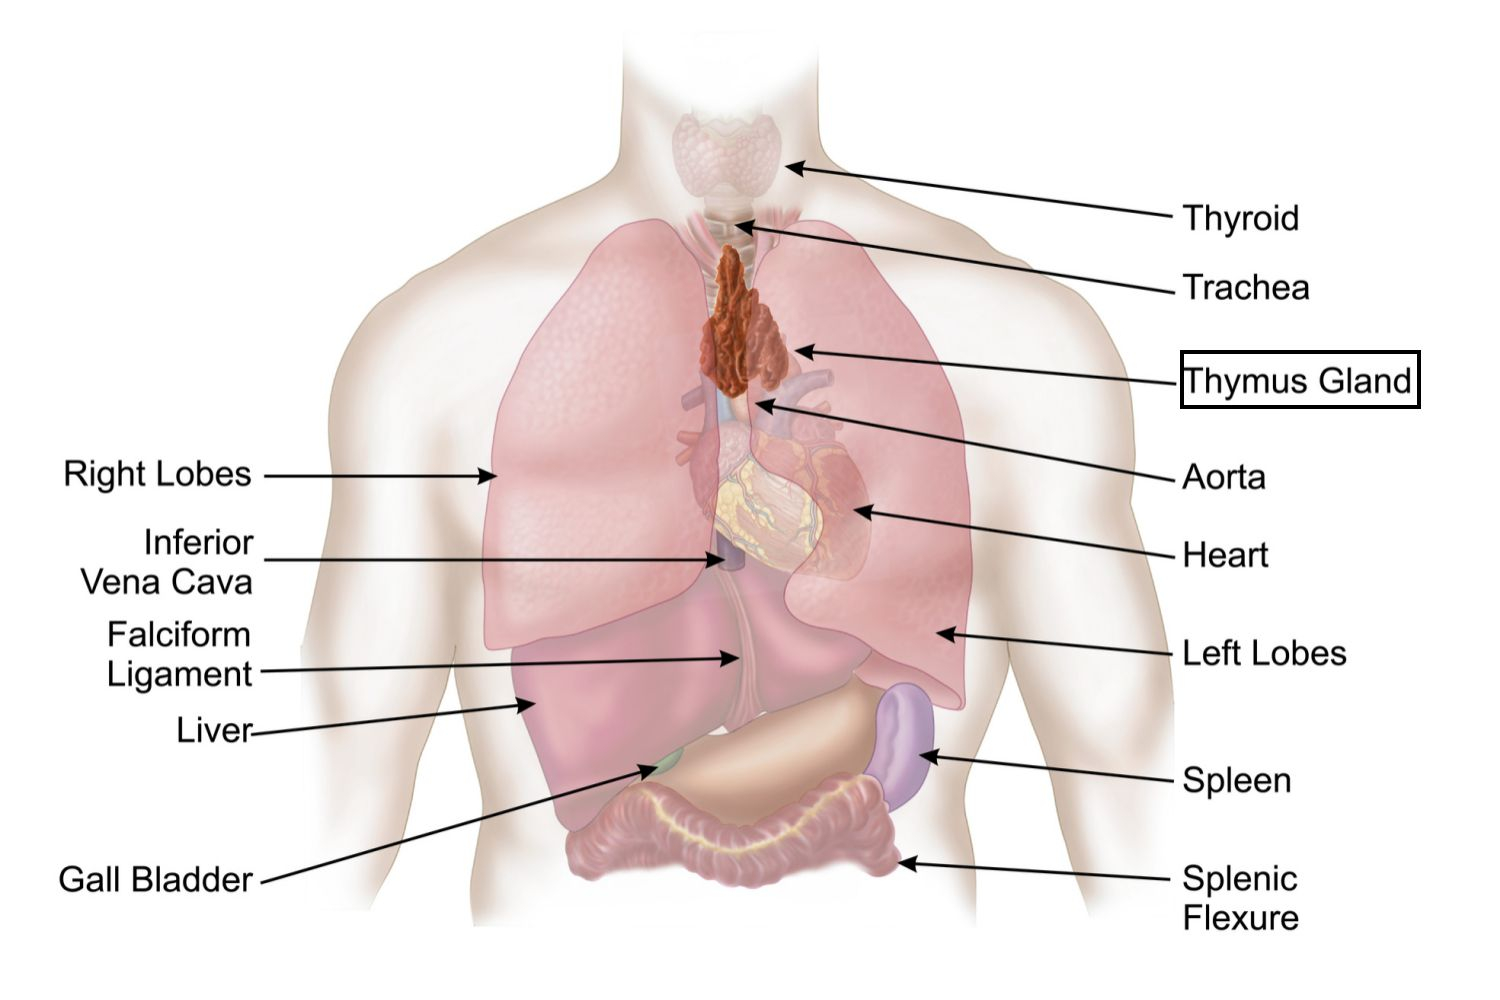

Фотографии вилочковой железы тимуса: структура и функции